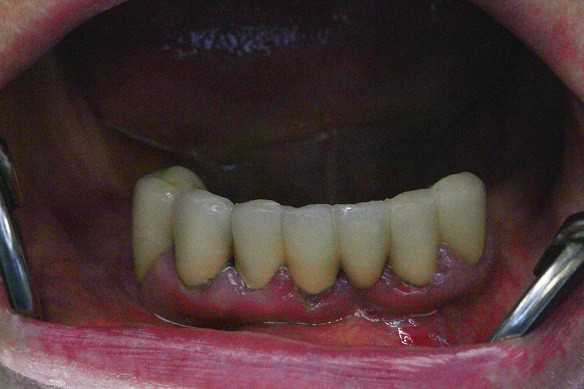

Жалобы: на отсутствие зубов, неудовлетворительную эстетику зубных рядов, невозможность жевать, подвижность зубов. Что сделано: удаление зубов на в/ч и н/ч, установка имплантатов Bredent Sky (верхняя челюсть 6 импл, нижняя 4 импл) и одномоментное протезирование акриловыми протезами с опорой на имплантаты по протоколу Fast & Fixed (зубы за один день). Через 10 месяцев проведена работа по замене протезов на постоянные металлокерамические. Что получил пациент: красивую улыбку, возможность нормально питаться с первого дня после операции.

Жалобы: на отсутствие зубов, неудовлетворительную эстетику зубных рядов, невозможность жевать, снижение высоты прикуса. Что сделано: удаление зубов на в/ч и н/ч, установка имплантатов Bredent Sky и одномоментное протезирование акриловыми протезами с опорой на имплантаты по протоколу Fast & Fixed (зубы за один день). Через 8 месяцев проведена работа по замене протезов на постоянные металлокерамические. Что получил пациент: красивые и ровные зубные ряды, возможность нормально питаться с первого дня после операции, поднята высота прикуса, теперь не стесняется улыбаться.